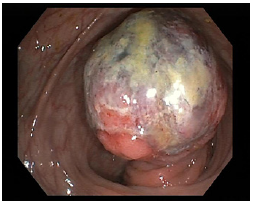

An otherwise healthy 55-year-old female patient with a family history of colon cancer presented to perform a total colonoscopy due to episodic abdominal pain and hematochezia for the past 1.5 months. It revealed an apparently pedunculated lesion of approximately 5 cm with superficial ulceration and friability in the transverse colon, which was primarily thought to correspond to a colonic neoplasia, mainly because of the presence of mucosal ulceration (Fig. 1). The lesion was biopsied.

Fig. 1 Endoscopic image showing a voluminous pedunculated colonic lesion with superficial ulceration.